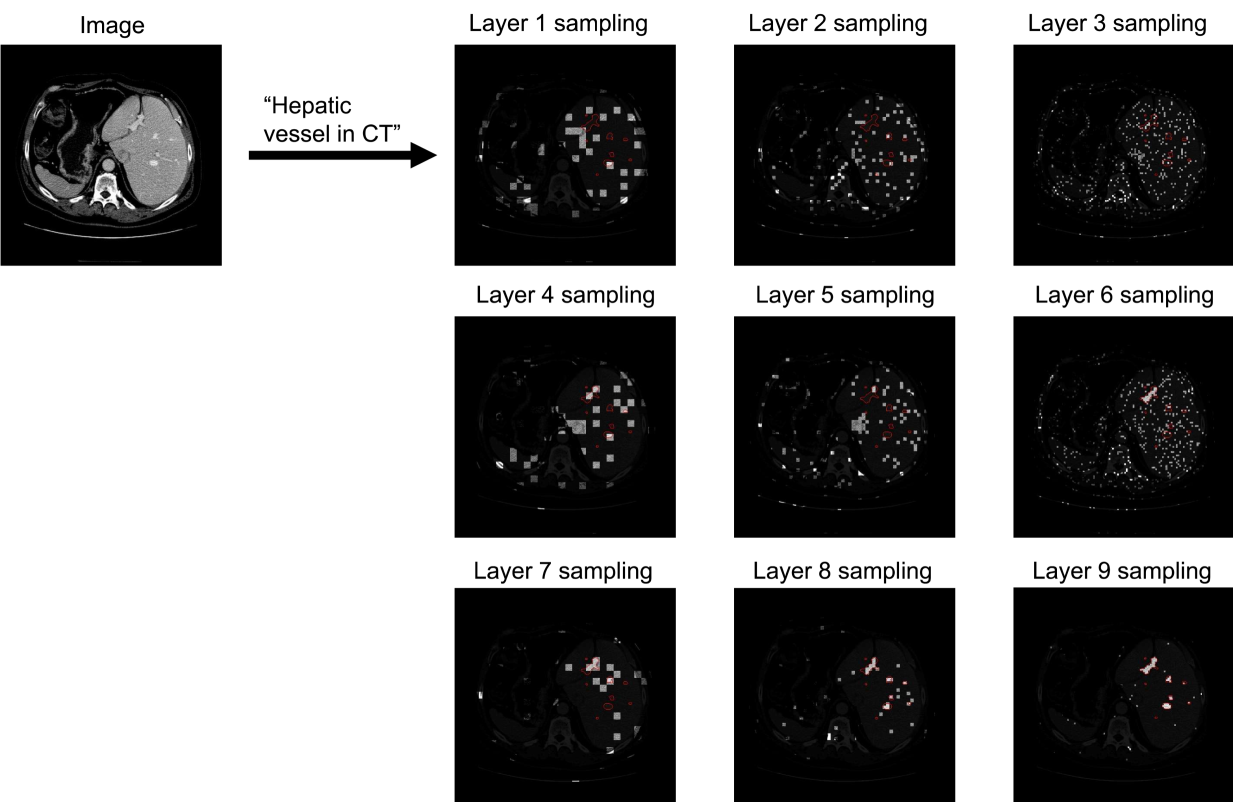

From Fig. 5, 6, 7 and 8 we can see that the sampling is wide spread during the early layers. The sampling began to concentrate towards the target region during the middle layers, while still exploring the other regions. At the final layers the sampling was highly concentrated on the target regions.

Figure 7: Boltzmann sampling example for hepatic vessel in CT. The sample patches are bright with target region circled in red.

We visualize the examples of Boltzmann attention sampling through the layers in BoltzFormer. In each layer, each query vector only attend to the sampled visual features visualized in the figures. We looped through the three scales of visual features for three times, resulting in nine layers in total. The shaded regions are completely invisible to the query in that layer. We show the Boltzmann sampling for the first query in the ensemble in these examples.